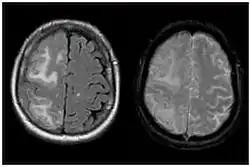

Two MRI scans demonstrating the difference between ARIA-E (left) and ARIA-H in the parietal region (right)